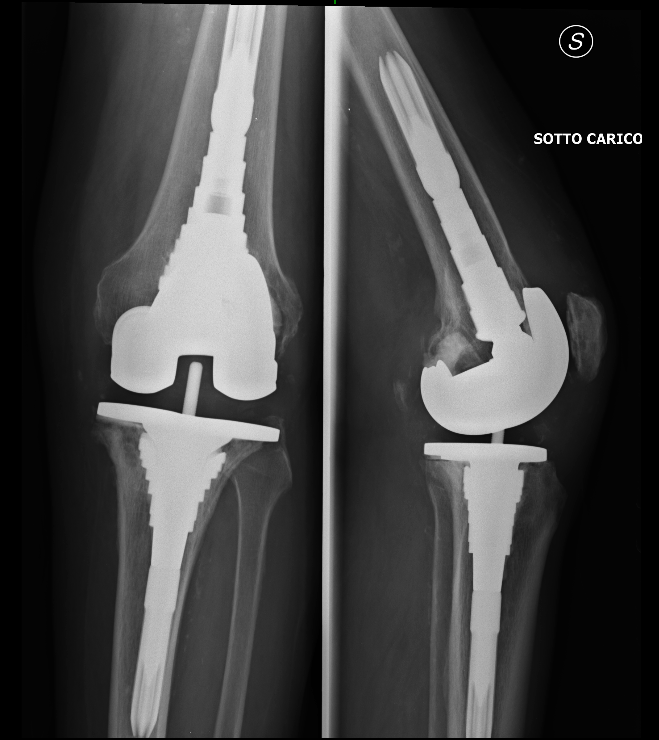

Le protesi al ginocchio utilizzate per la revisione sono, di solito, leggermente diverse da quelle usate nei primi interventi. Infatti, molto spesso le componenti per il femore e per la tibia presentano dei componenti più lunghi, che servono a fissarle meglio all’ osso. Talvolta, viene fatto uso anche di fili metallici, viti etc